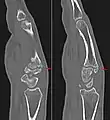

Carpal boss in CT.